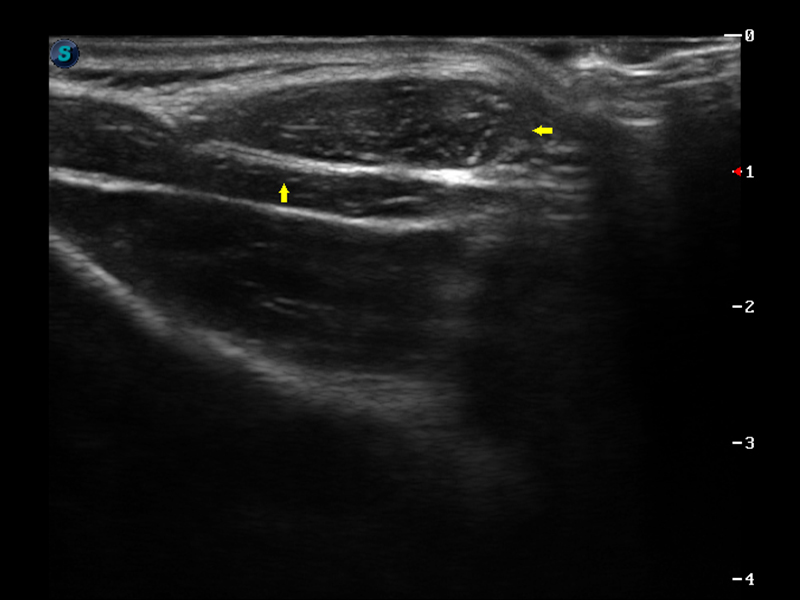

S9便携式彩色多普勒超声诊断仪是乐玩lewin国际研发的高端便携彩超设备,外观设计新颖、产品性能卓越。S9在便携超声领域采用了突破传统的触摸屏交互设计,并以先进的软件硬件技术和设计理念,为您带来清晰的图像质量、稳定的工作性能和便捷的操作体验。

μ-Scan微米成像